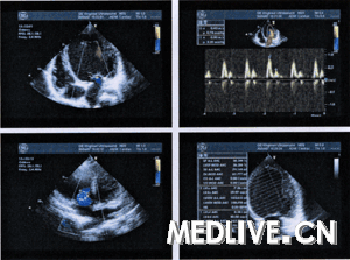

患者术前超声心动图,左室显着扩大